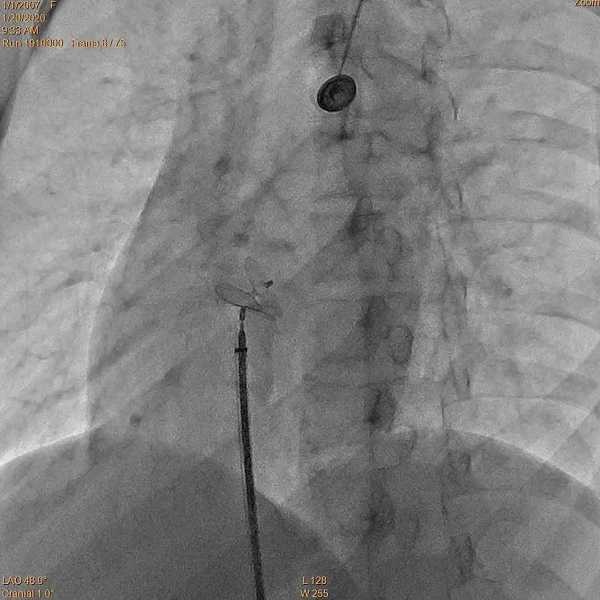

段师傅入院后,在介入组薛亦白副主任的安排下很快就完成了心脏彩超发泡试验检查,证实了高兴才主任的判断。为尽早解决患者痛苦,经积极准备,第二天由心脏外科介入组经验丰富的薛亦白副主任、张伟主治医师等为其实施卵圆孔未闭封堵手术,手术仅用时20分钟便顺利完成。术后第2天段师傅就可以下床活动,偏头疼缓解,术后第4天顺利出院。看着段师傅出院时的背影,连心脏外科的医护人员也都感受到他的那份轻松和愉悦。

手术方法:从大腿根部腹股沟区穿刺股静脉,从人体自身大血管路径(股静脉→髂外静脉→髂总静脉→下腔静脉→右心房→左心房)将封堵器送达并固定于未闭的卵圆孔处,PFO封堵术主体部分耗时约5-10分钟。术后无瘢痕,半年PFO平均闭合率可超过98%。